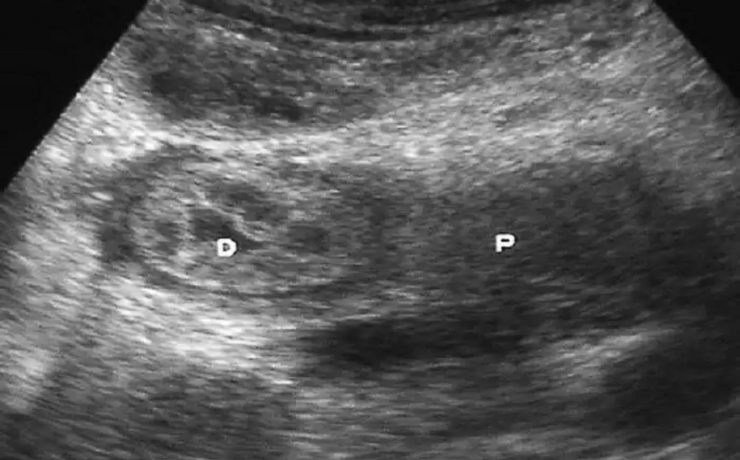

El parénquima esplénico tiene una ecogenicidad similar al hígado y menor que el riñón adyacente. Su valoración ecográfica es útil para confirmar la esplenomegalia y en el estudio de las lesiones esplénicas focales y de los traumatismos abdominales. El aumento del tamaño del bazo, que puede ser difícil de valorar